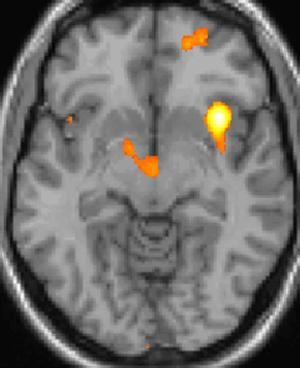

양전자 방출 단층 촬영술(PET) 이미지 2: 통증 중 활성화되는 뇌 영역

양전자 방출 단층 촬영술(PET) 이미지 3: 통증 중 활성화되는 뇌 영역

복셀 기반 형태 계측법 이미지 1: 뇌 영역의 구조적 차이

복셀 기반 형태 계측법 이미지 2: 뇌 영역의 구조적 차이

복셀 기반 형태 계측법 이미지 3: 뇌 영역의 구조적 차이

실제로 양전자 방출 단층 촬영술(PET) 스캔 연구 결과, 군발 두통 발작 중에 통증이 없을 때와 비교하여 시상하부의 특정 영역이 활성화되는 것이 관찰되었다. 또한, 복셀 기반 형태 계측법(VBM)을 이용한 연구에서는 군발 두통 환자와 그렇지 않은 사람 사이에 뇌 구조를 비교했을 때, 시상하부의 일부 영역에서 구조적인 차이가 발견되기도 했다.[35] 이러한 영상 연구 결과는 시상하부가 군발 두통의 발생과 관련이 깊다는 가설을 뒷받침한다.